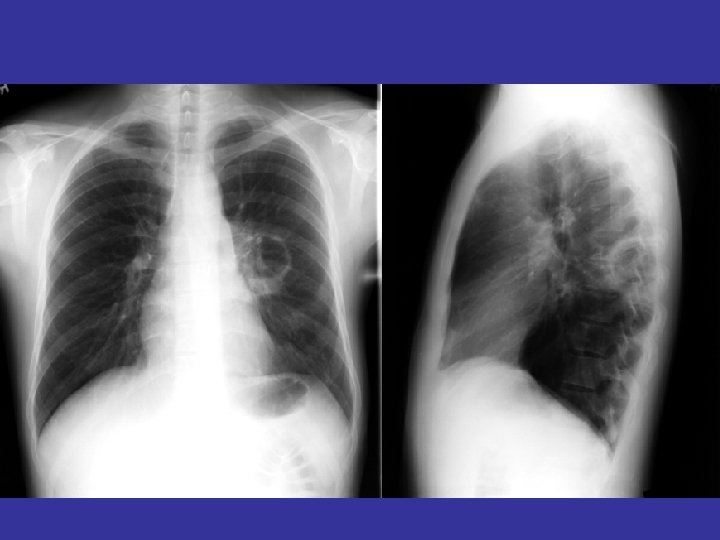

lateral view ? ! can detect otherwise hidden masses

The lateral chest film our best friend • Find abnormalities on the frontal film

The lateral chest film our best friend • Find abnormalities on the frontal film • Confirm abnormalities suspected from frontal film • Don’t be afraid to look at it